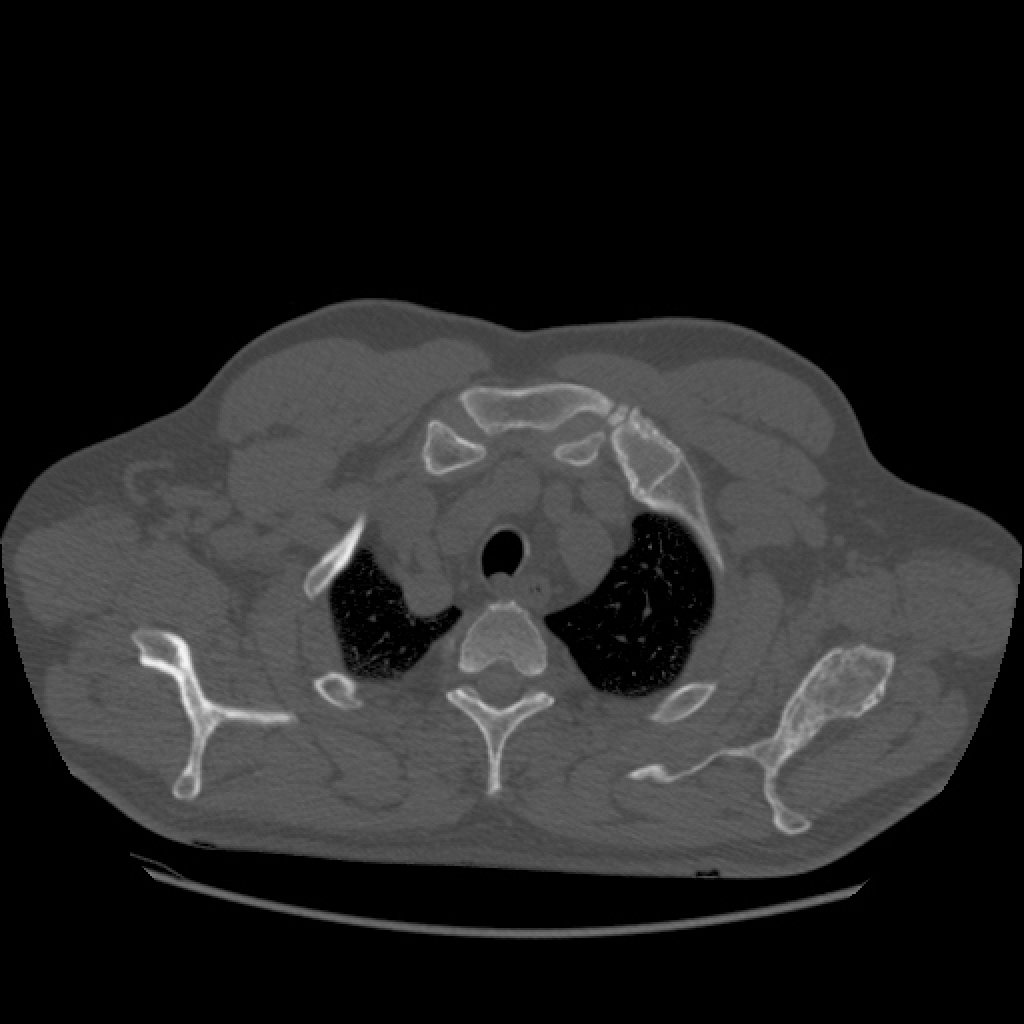

Рентгеновские снимки и визуализация болезни Педжета

Раздел: Мудрость в объективе